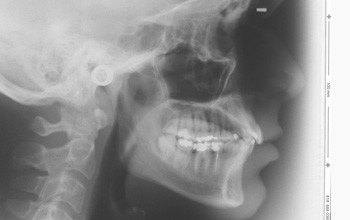

Ein 36-jähriger Patient stellte sich mit einer Klasse II/1 mit Engstand in beiden Kiefern vor (Abb. 1–7). Im Oberkiefer kamen hierbei folgende Bogensequenzen zum Einsatz: